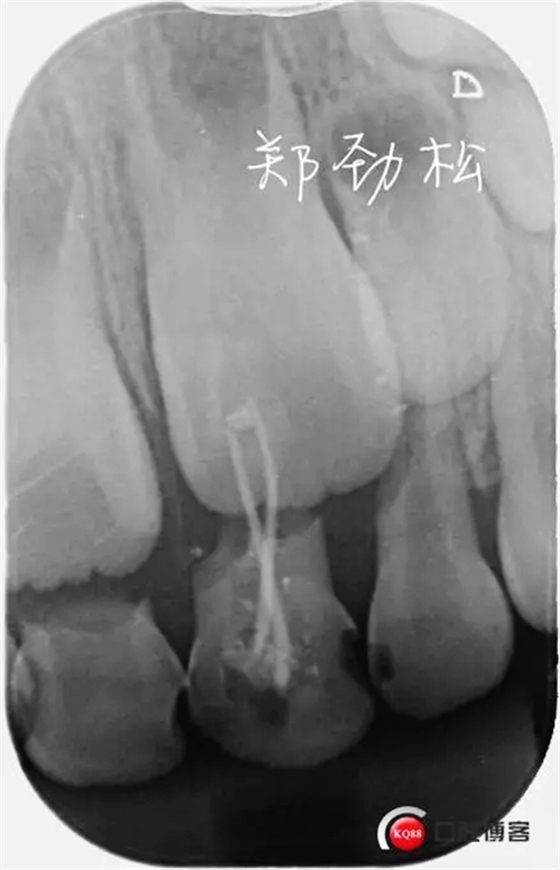

檢查:7A牙體變色,舌側有充填物,叩診(++),松一度,冷熱刺激無反應,唇側牙齦紅腫有一瘺管。

診斷:7A慢性根尖炎

處置:開隨,去除根充物后沖洗引流。

此病例術后取出根充物發(fā)現(xiàn)其中有兩根牙膠尖,其實大家都知道乳牙的牙根隨著恒牙的萌出會逐漸吸收,而牙膠尖不能被吸收,所以牙膠尖不能夠用作乳牙根充,我常規(guī)選擇vitapex糊劑作為乳牙的根充材料。